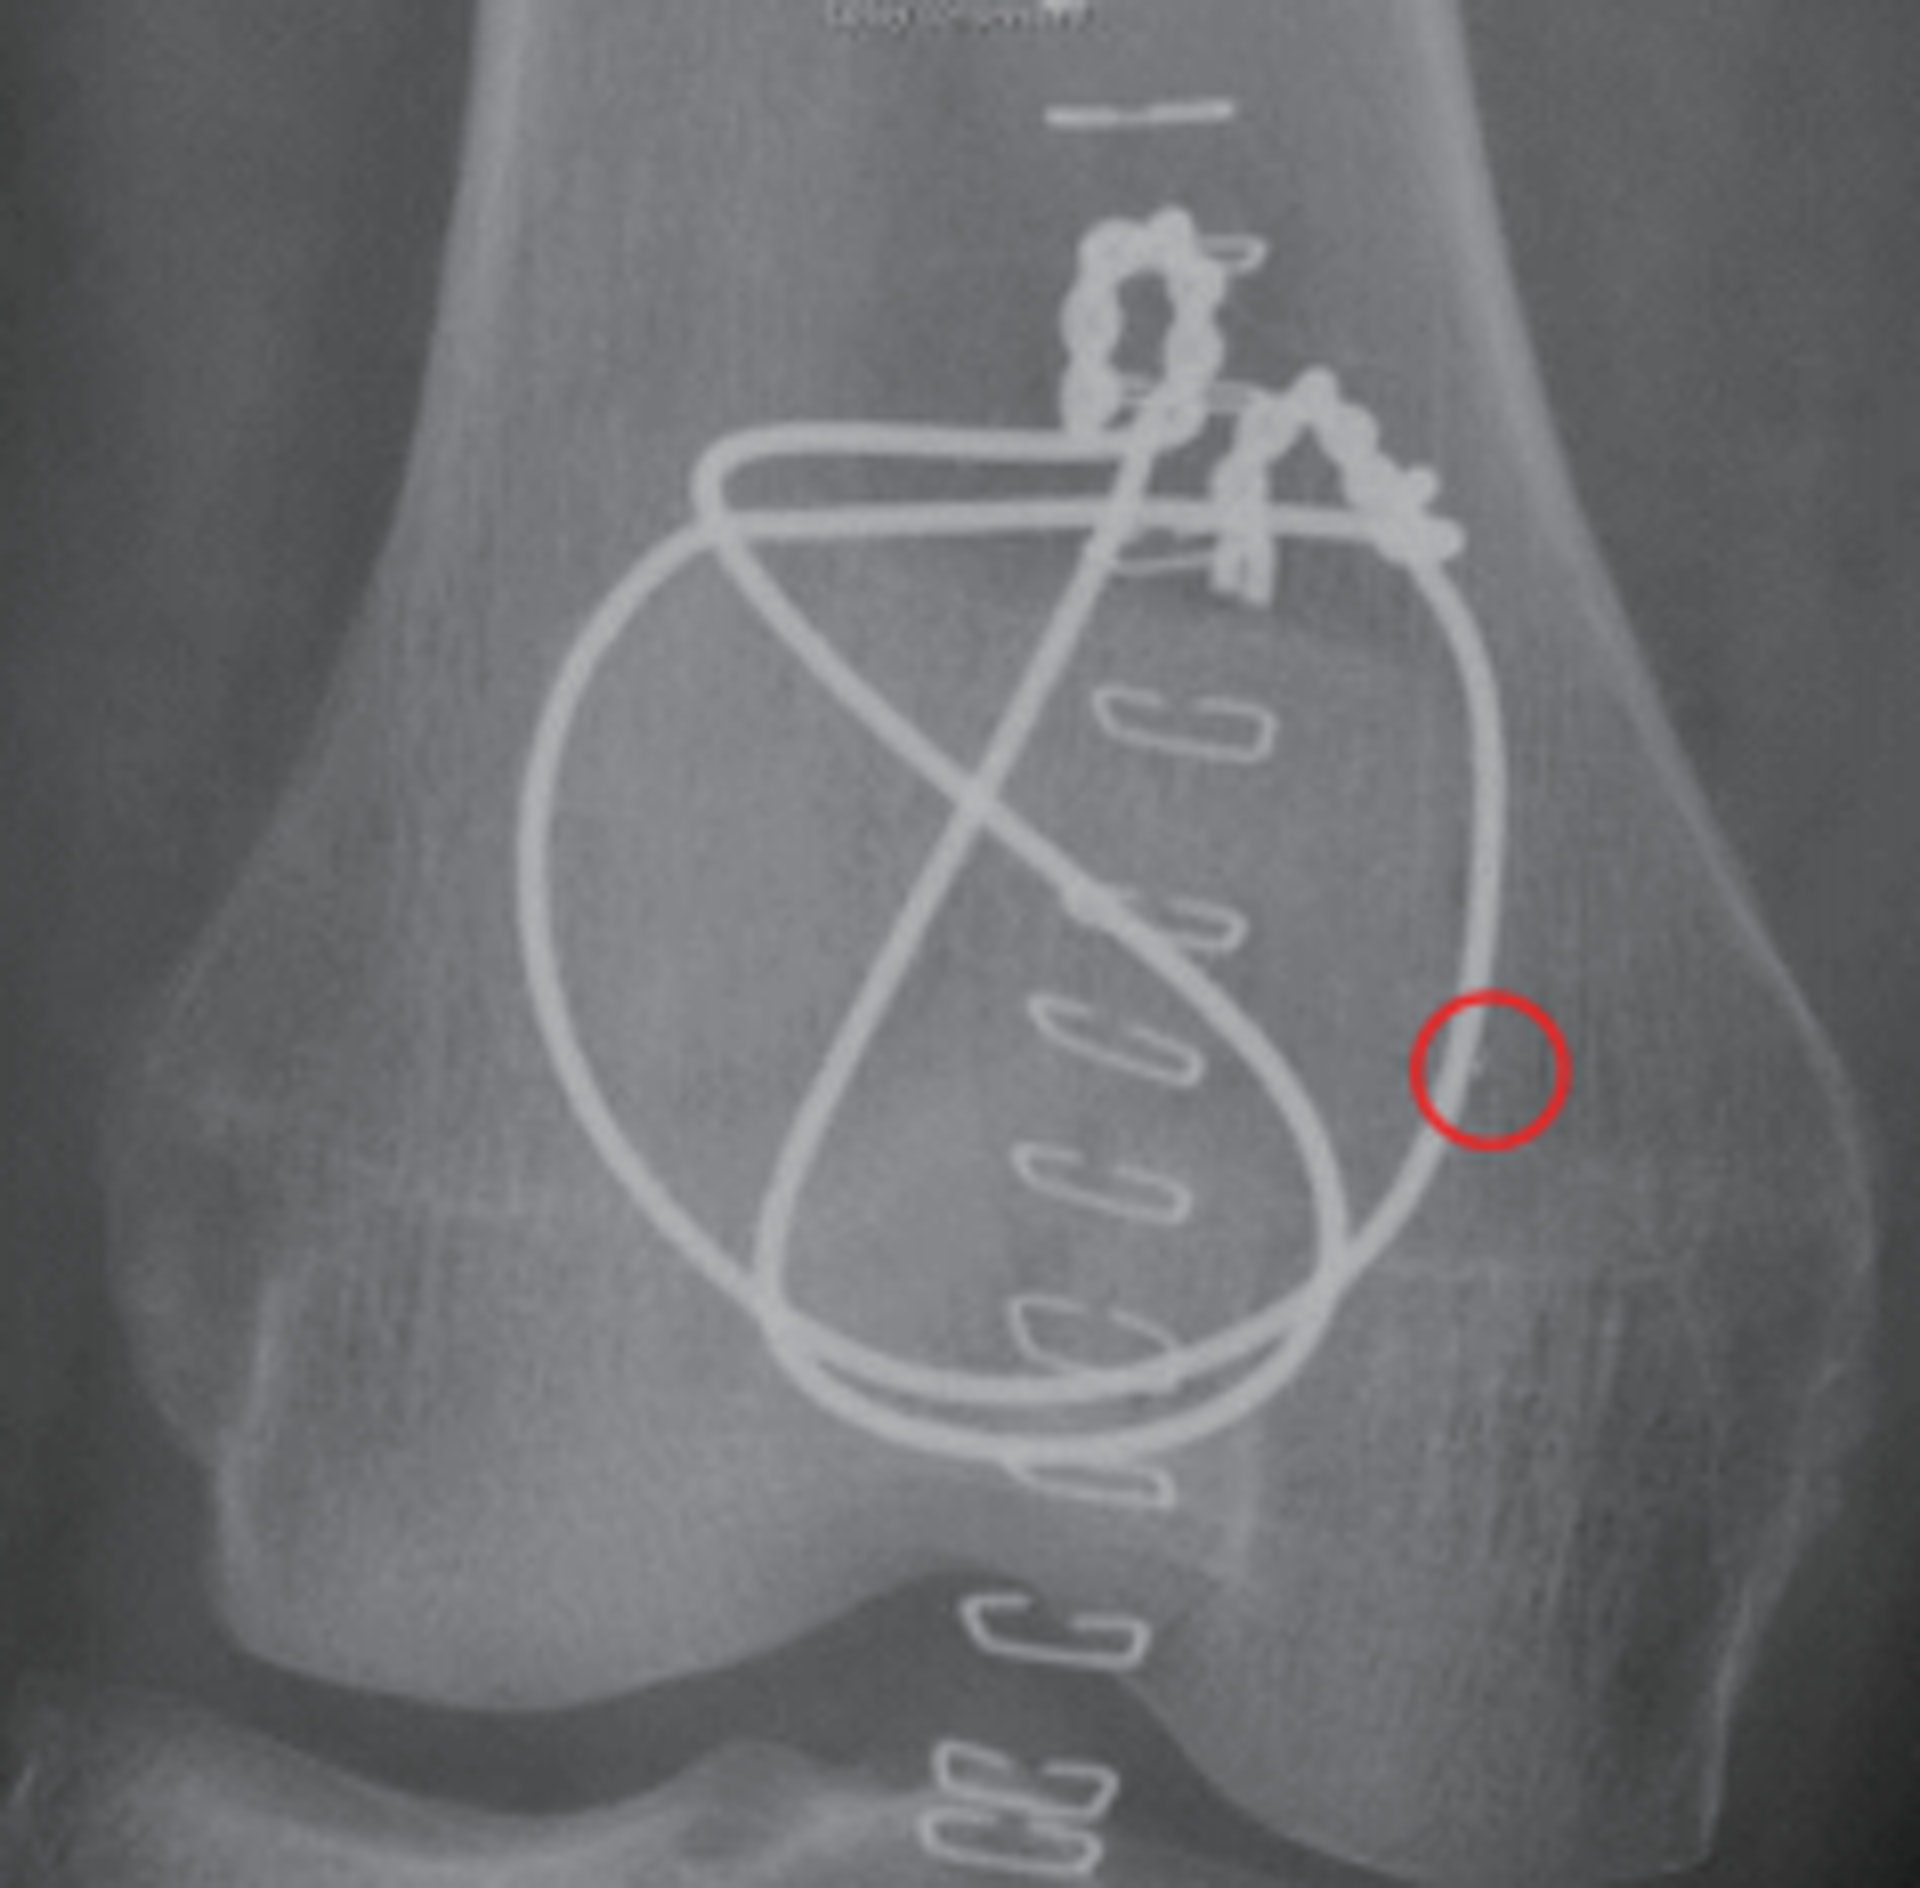

+ U7 l& t- |0 z6 stvb now,tvbnow,bttvb一位病人在術後發現右腳髕骨內側有異物。(風險通報圖片)

此外,風險通報中發現三宗涉及遺留醫療物料在病人體內的事故,漏留的物質包括導絲、紗布卷及一未被確定的異物。當中一名因右側髕骨骨折的患者進行手術固定,術後照X光發現患者右髕骨的內側發現0.9 x 0.4mm的異物,最後決定不移除異物。